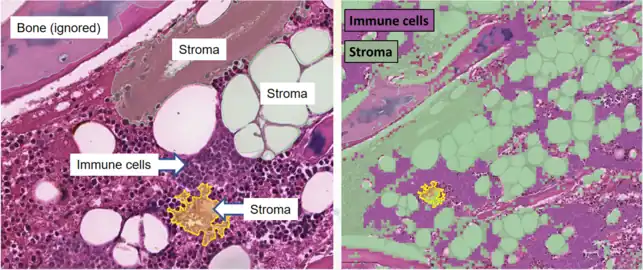

Tissue segmentation for digital calculation of bone marrow cellularity in QuPath: The system is trained on the appearance of immune cells versus other tissue, and uses this to give an overall percentage of each type.

Tissue segmentation for digital calculation of bone marrow cellularity in QuPath: The system is trained on the appearance of immune cells versus other tissue, and uses this to give an overall percentage of each type.